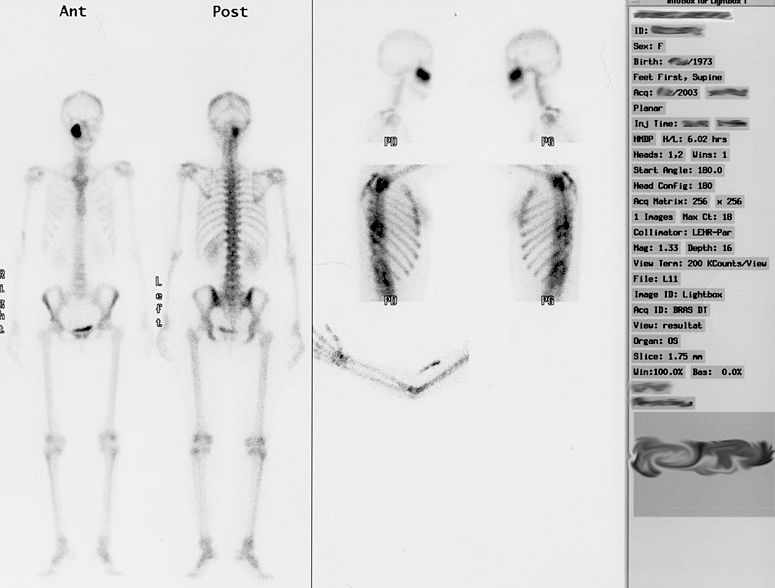

Gammagrafia o SPECT

La gammagrafia és una prova en la qual s’utilitza un radiofàrmac que s’introdueix dins l’organisme per via intravenosa i arriba a l’òrgan que es vol explorar. Aleshores la radiació que emet és captada per una càmera especial (gammacàmera) que produeix imatges funcionals i moleculars. Es poden veure en temps real com es mouen els òrgans i teixits, i veure els canvis que es produeixen a nivell molecular. La dosi de radiació és molt petita, igual o inferior a altres proves de radiologia.

Les exploracions més freqüents són les dels ossos, el cor, els ronyons, les tiroides, els pulmons i el cervell. Els usos més comuns són la gammagrafia d’ossos i la gammagrafia de tiroide (vegeu la figura).

Cal informar el metge o la metgessa si la persona usuària:

- Està embarassada o creu que pot estar-ho.

- Està donant el pit.